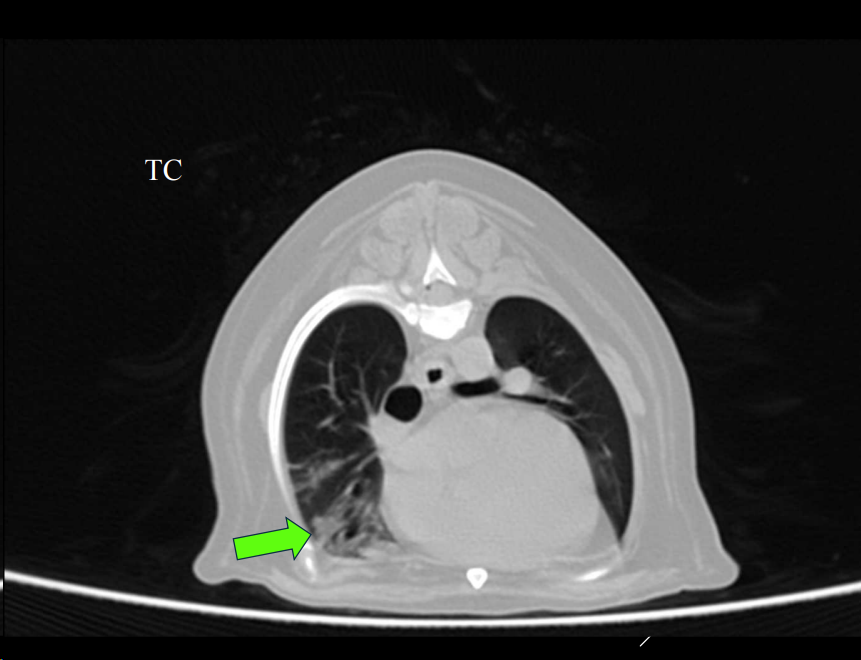

APLICACIONES DEL TC

- Detectar metástasis de pequeño tamaño o tromboembolismos pulmonares.

- Evaluar la lesión previo a cirugía.